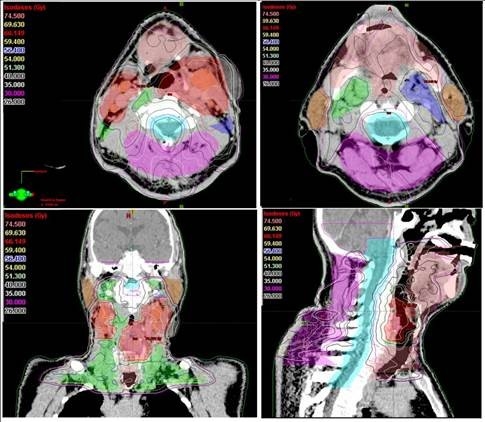

Antalya'da kanser kliniği uzmanlarından Radyasyon Onkolojisi Prof. Dr. Ali Aydın Yavuz, kanser hastalarının radyoterapisi sırasında "Yapay Zeka" uygulamalarının kanserde tedavi başarısını arttırdığını belirtti. Son yıllarda yapay zeka uygulamalarının kanser alanında kullanılmasına yönelik araştırmalarda artış olduğunu ifade eden Prof. Dr. Yavuz, "Tümör ve çevredeki normal dokuların üç boyutlu olarak sınırlarının çizildiği bu süreç, bir hastanın tümör bölgesine ne kadar radyasyon alacağını ve ışının en uygun nasıl odaklanacağını belirler. Özellikle ABD'nin Ulusal Sağlık Enstitüsünce desteklenen önemli bir araştırma projesinde "Yapay Zeka" kullanarak yüksek riskli tümör hedef hacimlerinin sınırlarının 3 boyutlu olarak belirlenmesi için her bir görüntüleme film kesitinde tümör ve normal doku sınırlarının tek tek çizilmesi (konturlama) işlemlerini otomatikleştirmek için yeni bir yöntem geliştirildi" dedi.

Bu çalışmanın sadece yüksek riskli tümör hacimlerinin "Yapay Zeka" ile otomatik bir şekilde ve çok yüksek doğrulukta belirlenmesine yönelik olduğunu dile getiren Prof. Dr. Yavuz, "Bir sonraki aşamada, eldeki tüm veriler birleştirilerek, orta ve düşük riskli tümör bölgelerinin de otomatik ve en doğru bir şekilde belirlenmesi mümkün olabileceği gibi, hastaya özgü en uygun radyoterapi veya kemoterapiyi de ayarlamak adına çeşitli genetik mutasyonlara ait bilgiler de bu yapay zeka uygulamasına entegre edilebilecektir. Bu şekilde, kanser tedavisi sonuçlarında başarı oranlarının artması da kaçınılmazdır. Yöntemin çok önemli bir avantajı da bizlere sunduğu yüksek hız ve verimliliktir. Normalde, örneğin bir baş boyun kanserinde, hedeflenen hacimleri belirlemek bir hekimin 1-4 saatini alır. Yapay Zeka kullanan özel bilgisayar sistemi ile hem bir dakikadan kısa bir sürede hedef hacimler belirlenebilmekte, hem de hekimden hekime değişebilen hata payları ihtimali tümüyle ortadan kalkmaktadır. Bu yöntem, özellikle, hedef hacim belirleme alanında tecrübeli uzman sayısının daha az olduğu düşük ve orta gelir düzeyindeki ülkelerde çok büyük bir kolaylık sağlayacaktır, ancak bu yöntemin ABD gibi gelişmiş ülkelerde de kanser tedavilerindeki yararlılık ve verimliliği çok artıracağı açıktır" şeklinde konuştu.